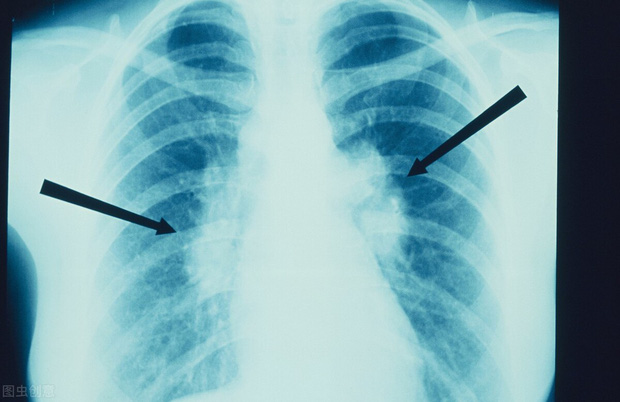

Khi đó, sau một đợt ho liên tục kéo dài và không thuyên giảm dù đã dùng nhiều loại thuốc khác nhau, ông Lu Tongfang cuối cùng đã đến bệnh viện để khám. Qua các xét nghiệm hình ảnh và giải phẫu bệnh, cuối cùng ông được chẩn đoán mắc bệnh ung thư biểu mô tuyến ở phổi giai đoạn cuối.

Dù vậy, chỉ sau 2 năm, vận đen lại ập đến. Tháng 5/2019, cha mẹ của ông Lu Tongfang tình cờ phải nhập viện do bị cảm nặng. Khi kiểm tra, bác sĩ phát hiện bố mẹ ông có bóng mờ rõ ràng trong phổi, nghi là ung thư phổi.

Sau hàng loạt xét nghiệm, kết luận cuối cùng đúng là như vậy. Điều này khiến ông Lu Tongfang không thể tin được, cha mẹ ông tuy đã già nhưng không bao giờ hút thuốc, uống rượu, cơ thể luôn dẻo dai, tại sao lại mắc bệnh ung thư? May mắn thay, khối u phổi của cha mẹ ông vẫn còn ở giai đoạn đầu, phẫu thuật có hy vọng chữa khỏi rất lớn.

Tìm hiểu bệnh sử, bác sĩ được kể về trường hợp bệnh của ông Lu Tongfang 2 năm trước thì ngay lập tức đề nghị vợ ông cũng nên đi khám. Lúc này, bác sĩ phát hiện ra rằng mặc dù vợ của ông Lu Tongfang không bị ung thư nhưng lại có nhiều nốt ở cả hai phổi. Vì các nốt ác tính thuộc loại ung thư phổi giai đoạn đầu nên sau khi được bác sĩ kiểm tra cẩn thận, một số nốt có thể có độ ác tính cao đã được loại bỏ.

Các nghiên cứu đã chỉ ra rằng 90% các ca ung thư phổi trên lâm sàng là do hút thuốc lá trực tiếp hoặc gián tiếp. Ngoài ung thư phổi, hút thuốc lá còn có thể gây ra hàng loạt bệnh ung thư khác như ung thư miệng, ung thư thực quản và ung thư gan. Vì vậy, chúng ta phải tích cực bỏ thuốc lá và không khuyến khích những người xung quanh hút thuốc.